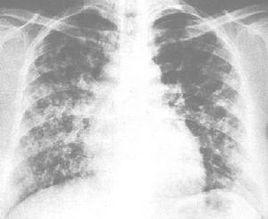

男,59歲。因慢性喘息性支氣管炎病史20餘年,發作半月而入院。患者半月前因受涼後咳嗽、咳痰及喘息症狀加重,在單位衛生所給予抗感染及對症治療,先後套用頭孢唑啉鈉、舒巴坦鈉/頭孢哌酮鈉等藥物治療,療效不佳,轉入我院。查體:體溫36.8℃,脈搏120/min,血壓150/90mmHg,呼吸26/min。口唇顏面明顯發紺,四肢、顏面水腫。桶狀胸,雙肺叩診呈過清音,聽診可聞及廣泛乾

藥物檢測性濕囉音,心率120/min,可聞及早搏;肝肋下2cm。X線胸片示雙肺透光度增強,肋膈角增寬,肺紋理增重,右下肺高密度片狀陰影,右肋膈角不清;右下肺動脈17mm,肺動脈段突出。血常規:紅細胞4.24×1012/L,白細胞12.7×109/L,中性粒細胞0.88;血氣分析:pH7.364,PO233mmHg,PCO262mmHg,HCO3-34.1mmol/L。入院診斷:慢性喘息型支氣管炎急性發作期;右下肺炎;Ⅱ型呼吸衰竭;慢性肺原性心臟病,心功能Ⅳ級。 入院後痰培養有綠膿桿菌生長,藥敏試驗顯示其對β內醯胺類藥物、氨基甙類藥物及喹諾酮類藥物均耐藥,但對亞胺培南-西拉司丁鈉(泰能)敏感。故給予泰能0.5g,每8小時一次靜脈滴注,連續使用4次,2天內共用泰能2.0g。用藥第2天,距第4次用藥5小時後,患者開始出現意識模糊、呼之不應或答不切題、幻聽幻視、狂躁不安、譫語、手足亂動等嚴重精神症狀,為防止患者的自我傷害行為,不得已使用繃帶將其四肢固定。經分析後認為上述臨床表現可能是泰能引起的嚴重精神障礙,立即停用泰能,經對症治療後患者進入睡眠,醒後症狀逐漸減輕,約24小時後基本恢復正常。